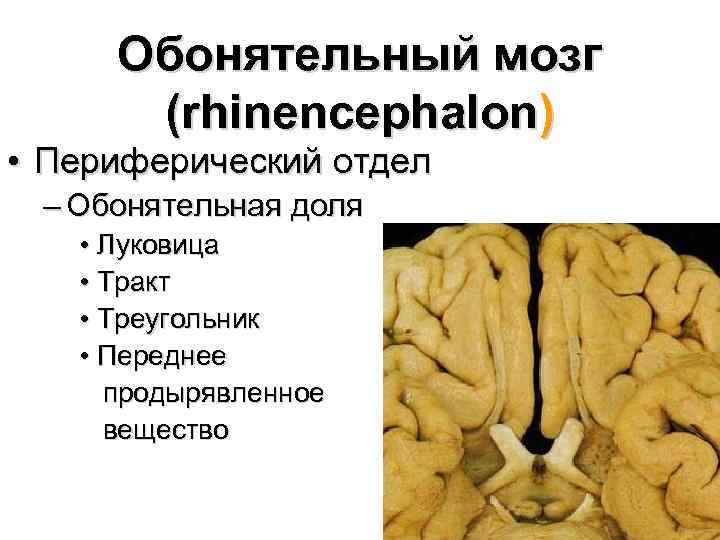

Необычные объекты: Переднее продырявленное вещество

Раздел: Альбом открытий